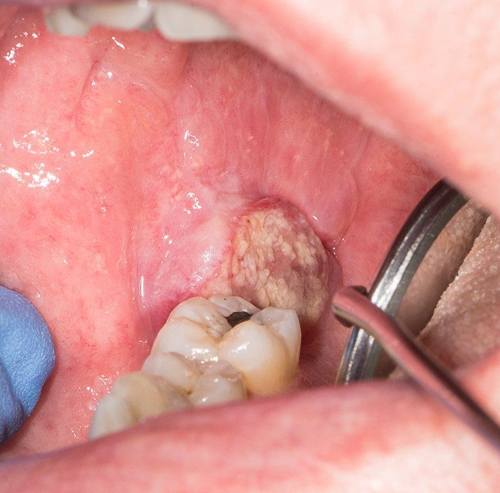

Oral cancer refers to cancer that develops in any part of the mouth, including:

• Inner lining of the cheeks

It usually begins as a small lesion or sore that doesn’t heal. If left untreated, it can spread to other parts of the mouth, throat, and even distant organs through the lymphatic system.

• A persistent sore or ulcer in the mouth

• White or red patches on the gums or tongue